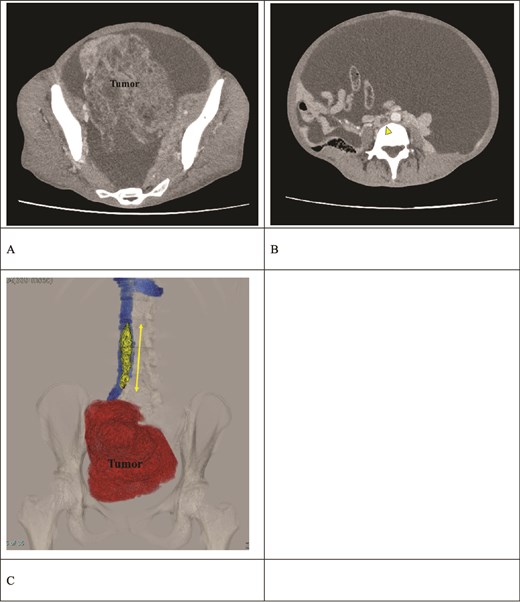

A 51-year-old woman who has never been pregnant presented with abdominal bloating for the past 3 months. The patient’s serum CA125 and CA19-9 levels were significantly elevated (112 080 and 178.25 U/ml, respectively). Computed tomography (CT) revealed a pelvic mass consistent with a right ovarian tumor suspicious for ovarian cancer (clinical stage IC: T1a N0 N0), in addition to massive ascites (Fig. 1A); however, elevated D-dimer levels of 10.72 μg/ml were detected, and lower limb ultrasonography revealed bilateral DVT. Contrast-enhanced CT revealed a thrombus in the IVC extending from the right iliac vein to the L2 level, accompanied by a peripheral left PE (Fig. 1B and C). The patient had not been receiving any anticoagulant therapy. Following admission, the patient received continuous intravenous heparin infusion to prevent the progression of DVT and PE.

Preoperative contrast-enhanced CT. (A) A right ovarian tumor is observed in the pelvic cavity. (B) Massive ascites and a thrombus (arrow) in the IVC are observed. (C) The 3D reconstruction image shows a venous thrombus (arrow) extending from the right iliac vein to the IVC at the L2 level. The distance between the renal vein and the thrombus tip is only 25 mm.